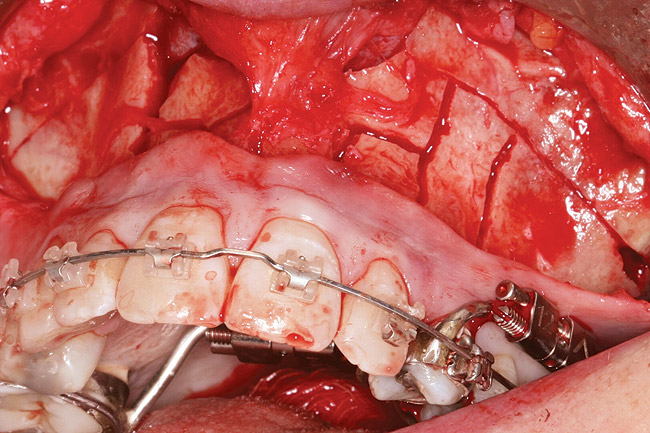

Fig 10. A corticotomy in SFOT is a surgical technique in which only the cortical bone is cut, perforated, or mechanically altered to the depth of the medullary bone and the medullary bone remains intact.

Figure 10

For describing the overall philosophies for the surgical techniques, the various facilitation procedures are divided into two categories: 1) those primarily using corticotomies or decortication and 2) those utilizing single- or multiple-tooth osteotomies. A corticotomy is a surgical technique in which only the cortical bone is cut, perforated, or mechanically altered to the depth of the medullary bone and the medullary bone remains intact. In contrast, an osteotomy consists of surgical cuts through both the cortical and medullary bone and typically indicates the creation of a bone segment. Table 1 differentiates between these two categories and outlines their various protocols.

The techniques in the corticotomy-facilitated category revolve around various methods of partially decorticating the alveolar bone housing the teeth to be moved (Figure 2 through Figure 10). Some of the techniques suggest buccal and lingual corticotomies19 while others recommend corticotomies just on the buccal to promote expansion. Some techniques routinely recommend extensive bone grafting in an attempt to facilitate bone development, while others do not. All of the corticotomy techniques primarily focus on weakening the cortical bone-tooth interface. Frost, an orthopedic surgeon, in his description of bone repair, suggested one of the desired effects of decortication.20 Physiologically, this theory proposes that when bone is injured or decorticated, it initiates a normal healing process with exuberant bone remodeling that is directly related to degree and proximity of the bone trauma. Frost named this process regional acceleratory phenomenon (RAP).20 Since then, this theory has been rigorously studied and proposed as a method of accelerating orthodontic treatment by other researchers.19,21-23 Numerous animal studies have shown up to a five-fold increase in medullary bone turnover in areas adjacent to corticotomy sites.24 It is speculated that this high medullary bone turnover in healthy tissues results in new bone formation and low bone density, which are conditions that promote rapid tooth movement with less root resorption.25 In addition, Chung et al and others claim that corticotomies combined with heavy forces lead to histologic changes called compression osteogenesis, in which the medullary bone of the decorticated segment can be bent to expand the traditional boundaries of orthodontic treatment.26